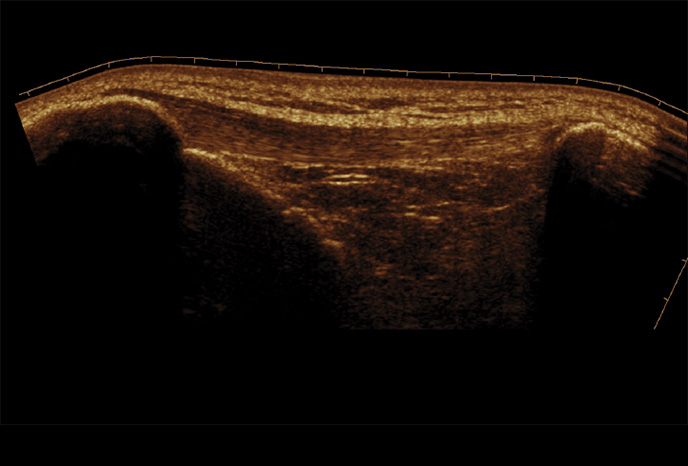

Filtr pro redukci šumu zlepšuje kvalitu 2D obrazu

Optimální diagnostický výkon zajišťuje filtr redukce šumu, který zajišťuje zvýraznění hran a vytváří ostřejší 2D obraz. O výrazné zlepšení kvality zobrazení se starají specializované technologie Samsung. ClearVison navíc poskytuje optimalizaci pro konkrétní aplikaci a pokročilé časové rozlišení v režimu živého skenování.